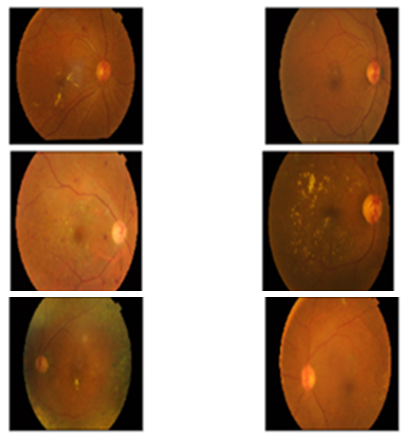

Figure 1. Different variation in diabetic retinopathy image for classification

To address the dimensionality and error rate of data in conventional selection and classification models, large and heterogeneous datasets are treated with feature selection based ensemble classification. Using the novel optimization functions, this optimal feature selection model is used to solve complex patterns. The main goal of this model is to increase the true positive rate of classification by reducing the error rate using the measure of hybrid feature selection as shown in Figure 1. Precise location of the boundary of the optical disc is a major sub-problem for the processing of ophthalmic images.